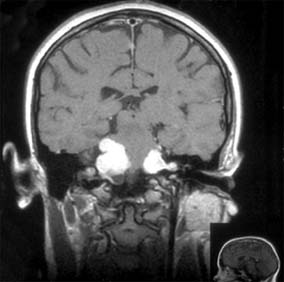

Neurofibromatosis is a generalized hereditary disease characterized by multiple tumors of the skin, central nervous system, peripheral nerves, and nerve sheaths. Other developmental anomalies, particularly of the bones, may be associated. There are two distinct dominant conditions. Neurofibromatosis 1 (peripheral) (Recklinghausen's disease) consists of multiple café au lait spots (99%), peripheral neurofibromas, and Lisch nodules (iris hamartomas) (93%), and its gene lies on the pericentromeric region of chromosome 17. The frequency is 1:3000 live births, with 100% penetrance. In neurofibromatosis 2 (central), there may be few or no café au lait spots or peripheral neurofibromas, but bilateral acoustic neuromas (vestibular schwannomas) are present (Figure 14-34) and its gene lies on chromosome 22. The frequency is 1:35,000. Neurofibromatosis 1 is associated with tumors primarily of astrocytes and neurons, whereas neurofibromatosis 2 is associated with tumors of the meninges and Schwann cells. There is no racial predominance. Signs may be present at birth but are activated during pregnancy, during puberty, and at menopause.

Figure 14-34

Figure 14-34: Coronal MRI of bilateral acoustic neuromas in neurofibromatosis 2.